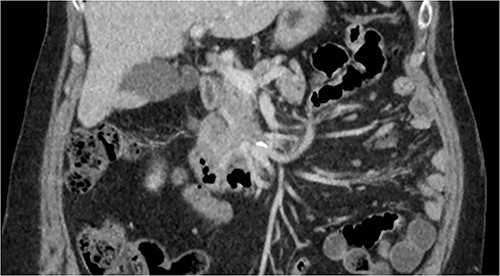

CT of abdomen and pelvis was performed, which revealed a 13 mm indeterminate lesion arising between the pancreatic uncinate process and the duodenum with coarse peripheral calcification, suspicious of primary pancreatic neoplasm or primary small bowel cancer (Figs 2–4).

Initial CT: coronal view of a 13 mm hyperattenuating region with peripheral calcification at the inferior margin of the pancreatic uncinate process and the superior margin of the duodenum.